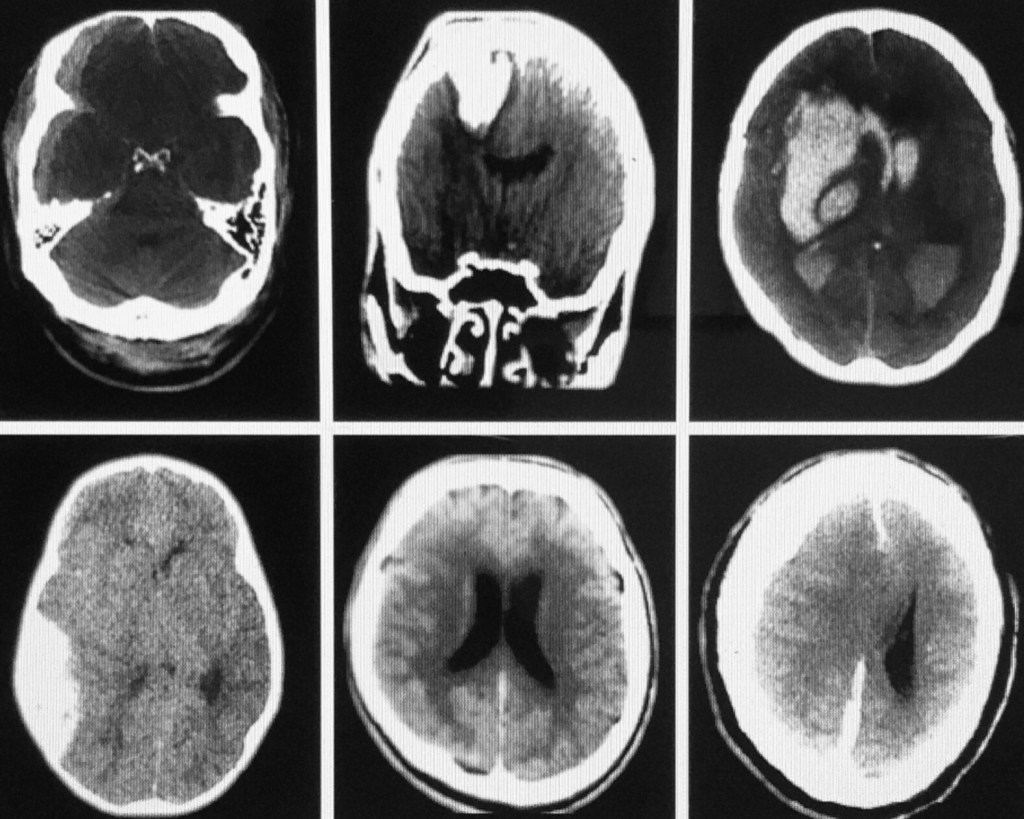

6 CT scans of the brain. Top Lt: Rt SDH w/occipital hematoma

Top middle: Penetrating injury w/round hematoma & surrounding edema.

Top Rt: Hypertensive Intracranial hemorrhage w/extension of blood into the posterior horns of the lateral ventricles bilaterally.

Bottom Lt: Acute Rt. EDH w/shift to Lt. [compression of 3rd ventricle].

Bottom middle: Diffuse global SAH w/convexity block [dilated ventricles].

Bottom Rt: Large acute SDH w/extension along the falx cerebrii, collapse of Rt. ventricle & shift of brain parenchyma to the Lt. From “The Complete EM Prep!” Written/illustrated by Dwight Collman MD. 1192 pages.